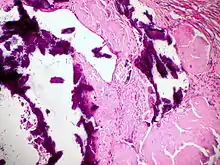

![]() Ausgeprägte Amyloidablagerungen (homogen rosa) in einem Lymphknoten, H&E. |

![]() Amyloidablagerungen in den Gefäßwänden, H&E. |

![]() Dystrophische Verkalkung (violett) bei Lymphknotenamyloidose, H&E. |